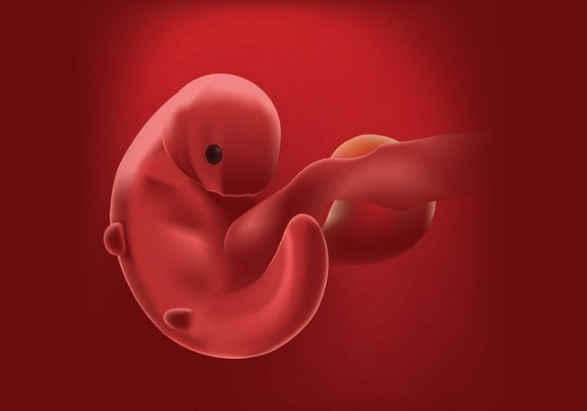

First, a tiny bit of science to ground us. At four weeks pregnant, you're technically in the second half of your first month. Conception happened about two weeks ago. Right now, the fertilized egg has travelled and implanted itself in your uterine lining. It's now called a blastocyst, and it's busy dividing like crazy. The part that will become the placenta is starting to form and produce the pregnancy hormone hCG (human chorionic gonadotropin).

This hCG is the star of the show. It's the hormone that turns a pregnancy test positive, and it's largely responsible for many of the early symptoms you might start to notice. Your body is just beginning to ramp up production, so levels are still relatively low but rising fast.